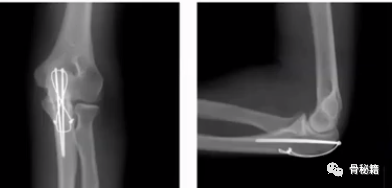

2、鹰嘴骨折